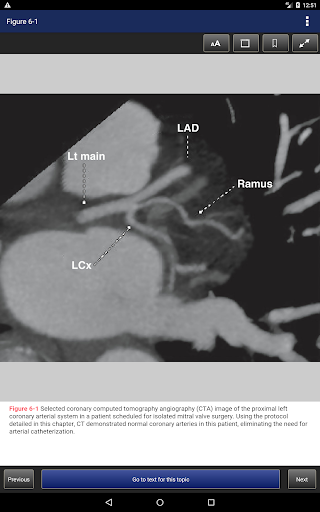

• Grundlagen (einschließlich Geschichte, Anatomie, Physiologie, Pharmakologie, berechnete Tomographie, Risikobewertung, Simulation und das vollständig integrierte kardiovaskuläre Zentrum)